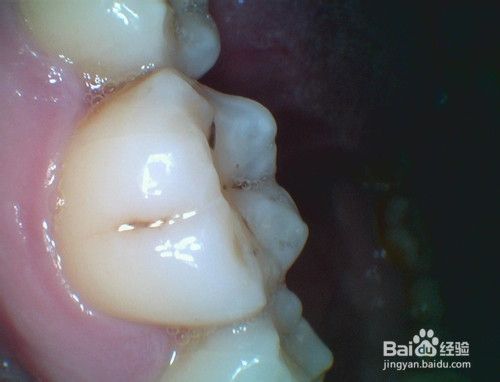

另一种牙劈裂的修复方法:树脂填充或纳米材料填充。这种主要针对牙劈裂缝比较小的情况。在局麻的情况下,直接填充缝隙或去髓根管治疗。

下图就是牙齿表面有裂缝需要填充修复的图片。